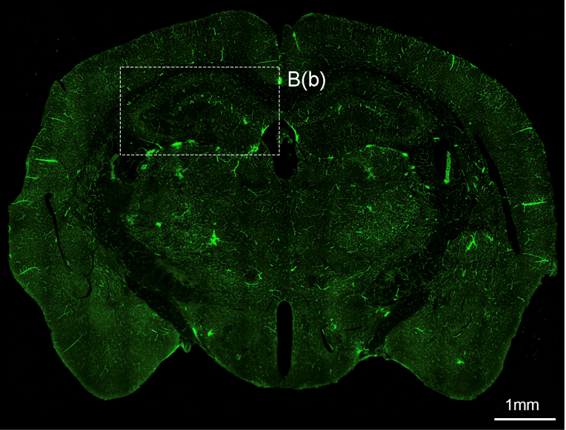

뇌혈관장애 및 퇴행성뇌질환 개선연구

- 연구주제 : 뇌혈관장애-유래 인지기능 저하 및 근감소증 제어기전 연구

- 연구주제 : 뇌경색 동물모델 구축을 통한 뇌혈관 장애 및 염증제어 후보물질 발굴